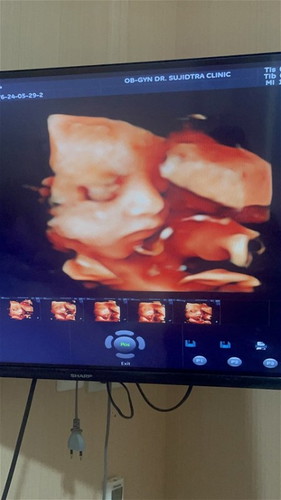

เห็นหน้าชัดมาก 😊

แต่น้องแอบหลับแต่ดีที่ให้เห็นชัด🥰